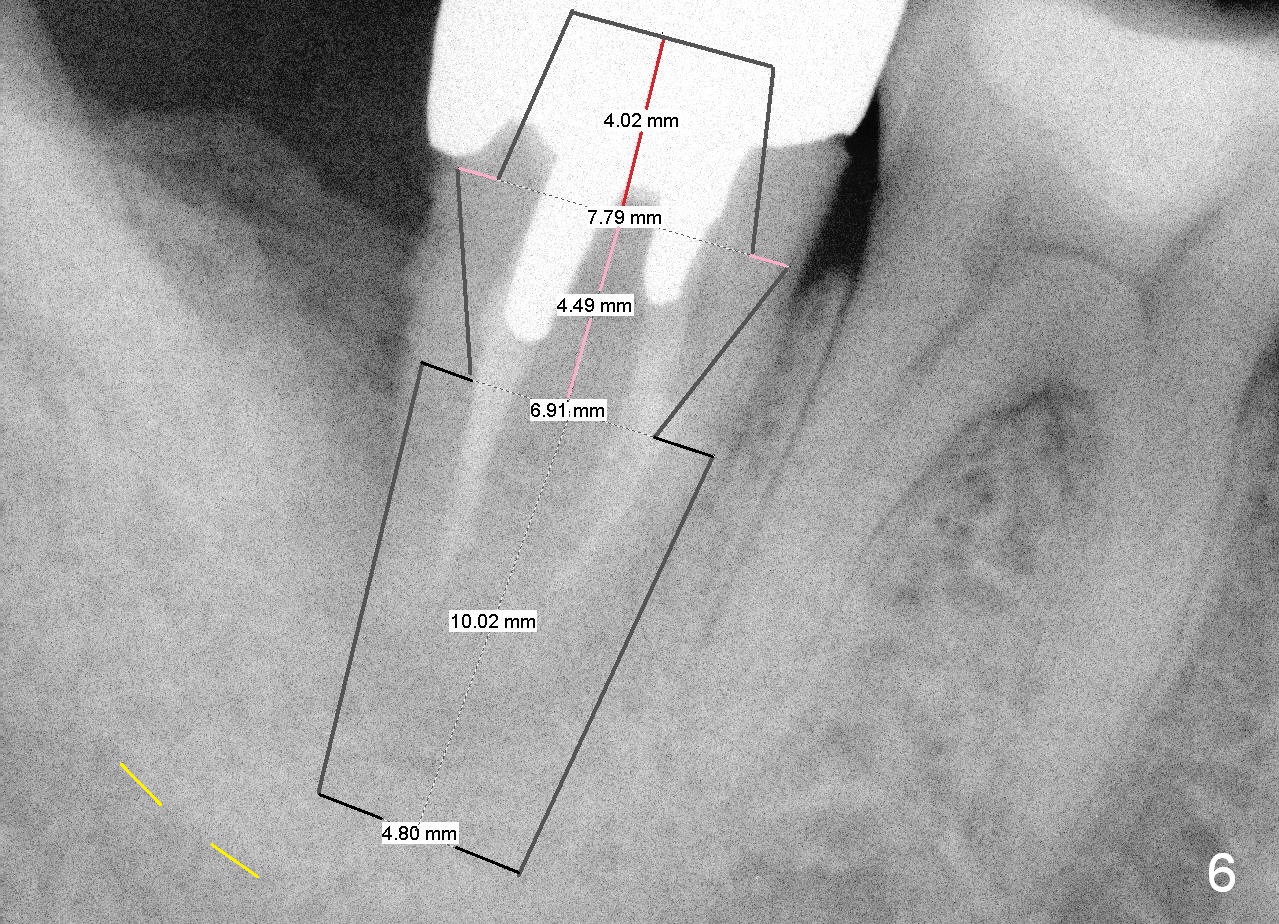

A 44-year-old man has had an asymptomatic distal defect of the tooth #31 for 8 years (Fig.1-5).  Recently there is an acute episode of swelling and pain.  A fistula develops mesiobucally.  Panoramic X-ray films tend to show that the distal defect is deep (Fig.2,5; yellow dashed line: upper border of the Inferior Alveolar Canal).  In addition, the distal defect may be not even buccolingually, as indicated by white and red arrowheads in Fig.3,4.  Following placement of a 6.9x10 mm bone-level implant, a 7.8x4 (4.5) mm cemented abutment is inserted for try in (Fig.6).  When it is fit, it is removed and a cover screw is temporarily placed.  A piece of Osteotape (~10x4 mm) is placed distobuccally or distolingually (depending upon which wall is lower).  A small amount of bone graft is packed between the most coronal portion of the implant and the Osteotape.  The cover screw is then removed and the abutment is re-inserted and tightened by hand.  An immediate provisional is fabricated with well-trimmed margin.  Reline is done if necessary for securely holding bone graft in place.  A new PA is to be taken prior to surgery to determine the extent of the lesion.  Photos are taken to show the mesiobuccal fistula.  Return to Lower Molar Immediate Implant Xin Wei, DDS, PhD, MS 1st edition 04/12/2015, last revision 05/25/2018